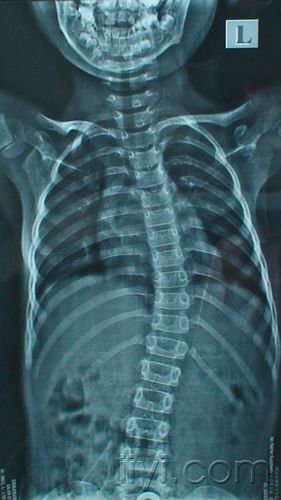

脊柱侧弯,最应该知道的那些事!

请专家们看看六岁小女孩的脊柱片子

儿童脊柱侧弯

儿童脊柱弯曲图片

儿童脊柱侧弯真人图片

儿童脊柱侧弯10度照片